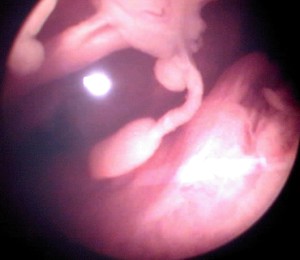

Artritis Idiopática Juvenil, visión artroscópica (1/11)

Sinovitis compatible con AIJ, Fase de establecimiento

Cortesía de la Dra. Dolores Cantera Oceguera cantera@infomed.sld.cu